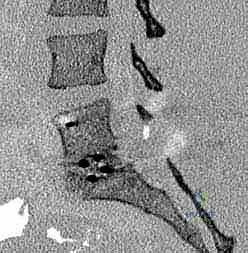

لفهم كيفية عمل تقنيات PLIF و TLIF، يجب أولاً فهم تشريح العمود الفقري القطني. يتكون الجزء السفلي من الظهر من خمس فقرات قطنية (L1 إلى L5). بين كل فقرة وأخرى يوجد "قرص غضروفي" (Disc) يعمل كوسادة لامتصاص الصدمات وتسهيل الحركة. يمر الحبل الشوكي والأعصاب الشوكية عبر قناة عظمية تُسمى "القناة الشوكية".

عندما تتآكل هذه الأقراص الغضروفية بسبب التقدم في العمر أو الإصابات، أو عندما تتحرك الفقرات من مكانها الطبيعي، يحدث تضيق في القناة الشوكية أو ضغط مباشر على جذور الأعصاب. هذا الضغط الميكانيكي هو المسبب الرئيسي للألم المبرح الذي يمتد غالبًا إلى الساقين (ما يُعرف بعرق النسا).

- تضيق القناة الشوكية القطنية (Lumbar Spinal Stenosis): تضيق المساحة التي تمر بها الأعصاب بسبب النتوءات العظمية أو تضخم الأربطة، مما يسبب ألماً شديداً عند المشي أو الوقوف.

- الانزلاق الفقري (Spondylolisthesis): انزلاق فقرة فوق الفقرة التي تحتها، مما يسبب عدم استقرار ميكانيكي وضغطاً عصبياً.

- مرض القرص التنكسي (Degenerative Disc Disease): تآكل الغضاريف بشكل حاد يؤدي إلى احتكاك العظام ببعضها البعض.